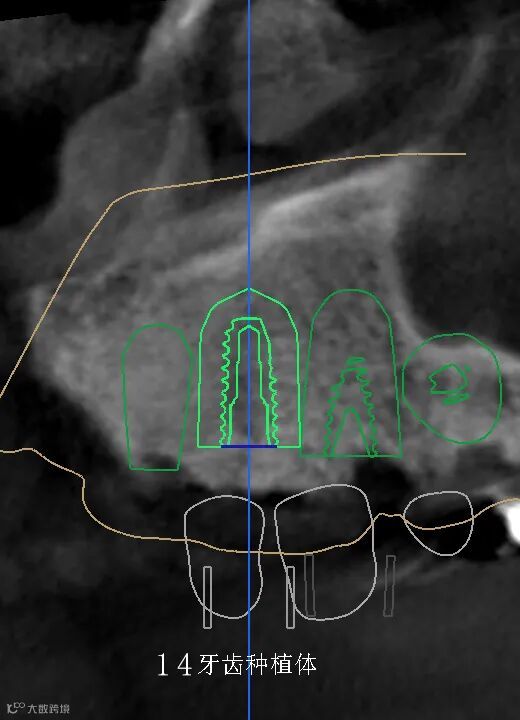

数字化种植手术规划与导板设计

精准——术前精确设计,术中精准控制,避免损伤重要的解剖结构,实现安全种植,以美学修复为导向,为永久修复牙位设计更理想、美观。